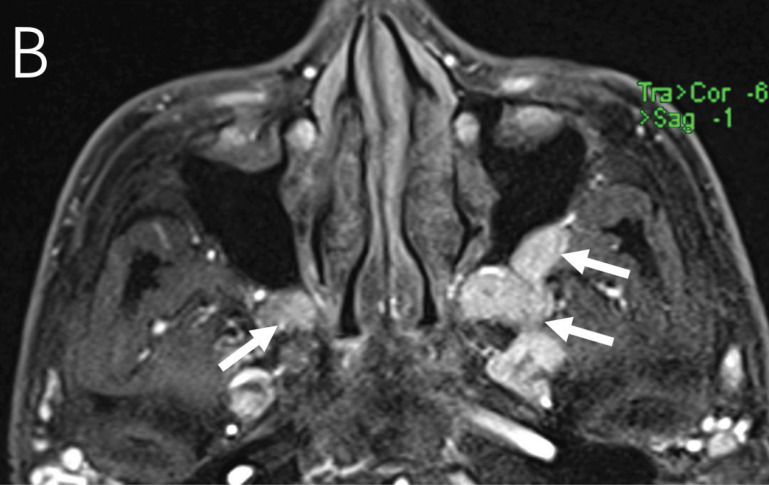

教学要点:免疫球蛋白G4相关性眼病(IgG4 - ROD)可能仅表现为三叉神经眶支弥漫性增厚。

Teaching point: Immunoglobulin G4‑related ophthalmic disease (IgG4‑ROD) may present only as diffuse thickening of the orbital branches of the trigeminal nerve.